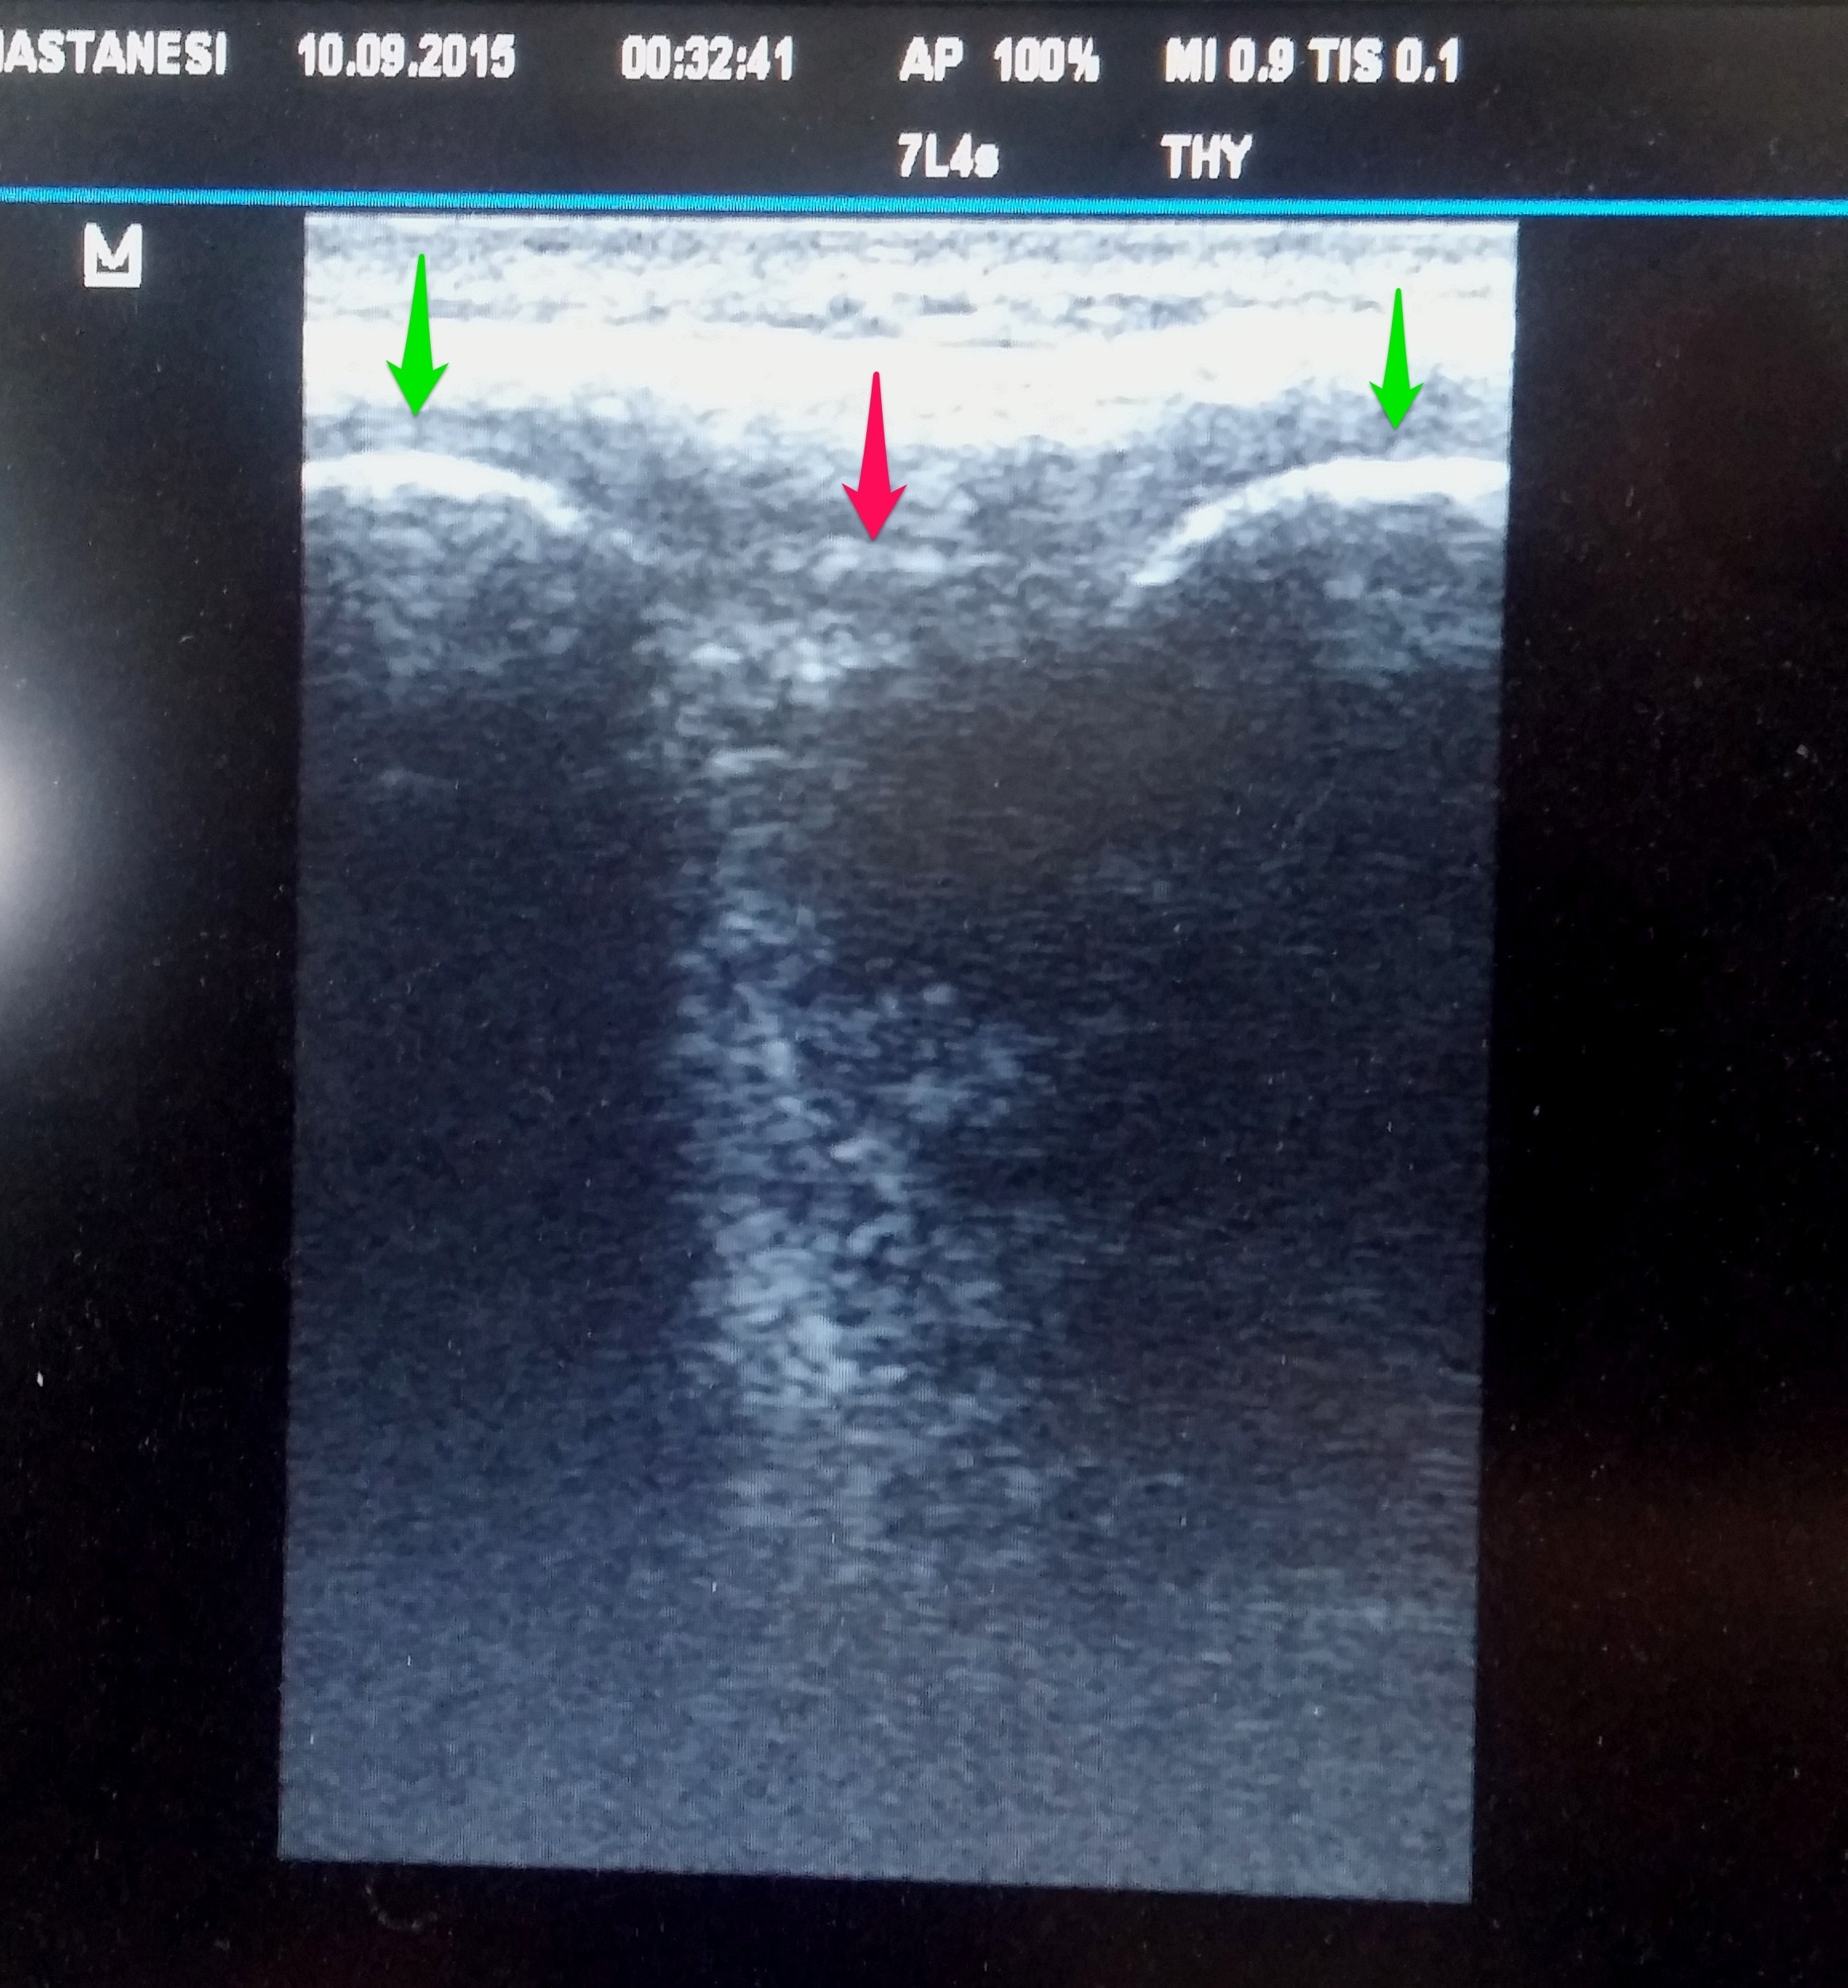

[box type=”info” align=”” class=”” width=””]Longitudinal kesit görüntüsü. Yeşil oklar: Spinöz çıkıntılar. Pembe ok: interspinöz ligaman[/box]